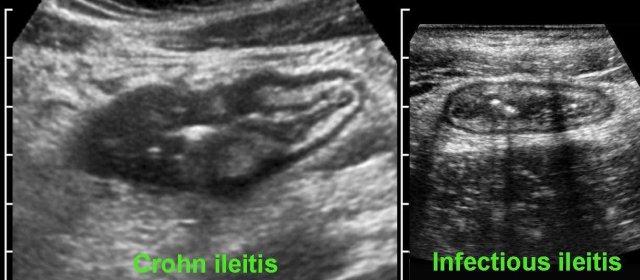

Differentiating Crohn’s disease and infectious ileocolitis is usually easy, as in the latter the layer structure is virtually always intact and  there is never inflamed fat, abscess or fistula formation.

Differences between Crohn’s disease and infectious ileocolitis.

However, differentiation of early Crohn’s disease from infectious ileocolitis, can at times be difficult to impossible.

Follow-up and repeated stool cultures in such cases can solve the problem.